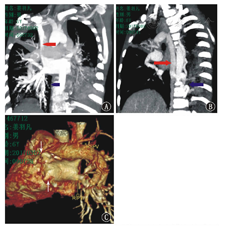

入院查体:神志清,精神欠佳,生长发育落后,营养不良貌;双眼微凸、下颌前突,面色苍白,口唇无发绀,双眼睑、阴囊、双下肢凹陷性水肿,口腔黏膜见广泛不易拭去白斑及散在溃疡,20枚黑色龋齿,咽充血,双侧扁桃体Ⅱ度;呼吸急促,轻度三凹症,双肺闻及广泛中细湿啰音;心音有力,腹膨软,腹壁静脉显露,有轻度压痛,无反跳痛,肝右肋下2.5 cm,质软,脾未触及,移动性浊音阳性;杵状指(趾)。辅助检查:肌内注射粒细胞集落刺激因子(G-CSF)前:10次ANC (0.21~0.46)×109/L (正常范围2×109/L~7×109/L)、单核细胞(0.82~2.94)×109/L (正常范围0.12×109/L~0.80×109/L);CD3 56.49% (59.00%~84.00%)、CD4+ 27.99% (31.00%~60.00%)、CD8+ 30.06% (13.00%~38.00%)、CD4+/CD8+ 0.93 (0.90~3.60)、B淋巴细胞(BLC)40.27% (7.00%~22.00%);IgA 7.63 g/L (0.58~1.00 g/L)、IgM 1.1 g/L (1.1~1.8 g/L)、IgG 37.70 g/L (6.60~10.39 g/L);自身抗体全套及染色体核型等均未见异常;入院时清蛋白19 g/L;5次痰培养大肠埃希菌生长、1次白色念珠菌生长;Epstein-Barr病毒(EBV)衣壳抗原-IgA、IgG及核抗原IgG均阳性,血EBV-DNA 6.47×106 copies/L。G试验997.3 ng/L (>100.0 ng/L)。骨髓细胞形态学:粒系增生减低,中晚幼粒细胞、杆状核及分叶核明显减低,单核细胞增生活跃。影像学:(1)双肺炎症,右上肺脓肿,胸腹腔积液;(2)迷走左椎动脉、奇静脉扩张,主动脉旁侧支血管迂曲增粗,下腔静脉肝段缺如,左肺静脉未显示(图1)。电子支气管镜:右上支气管黏膜内血管增粗凸出、搏动(图2)。武汉康圣达医学检验所使用安捷伦外显子芯片捕获+高通量测序:(1)ELANE基因(c.641G>A,p.G214E)(图3A),父母均无此突变(图3B、图3C)。(2) SH2D1A基因(c.7G>T,p.A3S)(图3D),父亲无此突变(图3E)。遗传自母亲(图3F)。未发现其他基因异常。诊断:伴SH2D1A基因突变的ELANE基因突变相关的综合征性SCN、重症肺炎。治疗:予保护性隔离,先后予"美罗培南、利奈唑胺、伏立康唑、复方磺胺甲

Cardiography of child with severe congenital neutropenia caused by ELANE and SH2D1A mutation

注:MIP:最大密度投影;A:冠状位MIP图,红箭头示上腔静脉蓝箭头示下腔静脉未见;B:矢状位MIP图,红箭头示扩张奇静脉,蓝箭头示迂曲增粗侧支血管;C :VR重建图,左侧肺动静脉细小,右侧肺动静脉形态正常MIP:maximum intensity projection;A:coronal MIP map, the red arrow shows the superior vena cava, the blue arrow shows no inferior vena cava;B: sagittal MIP reconfiguration, the red arrow shows dilated azygos vein, the blue arrow shows tortuous dilated collateral vessels;C: virtual reality reconstruction images, the arrows shows the left pulmonary arteriovenous is small, the right pulmonary arteriovenous is normal